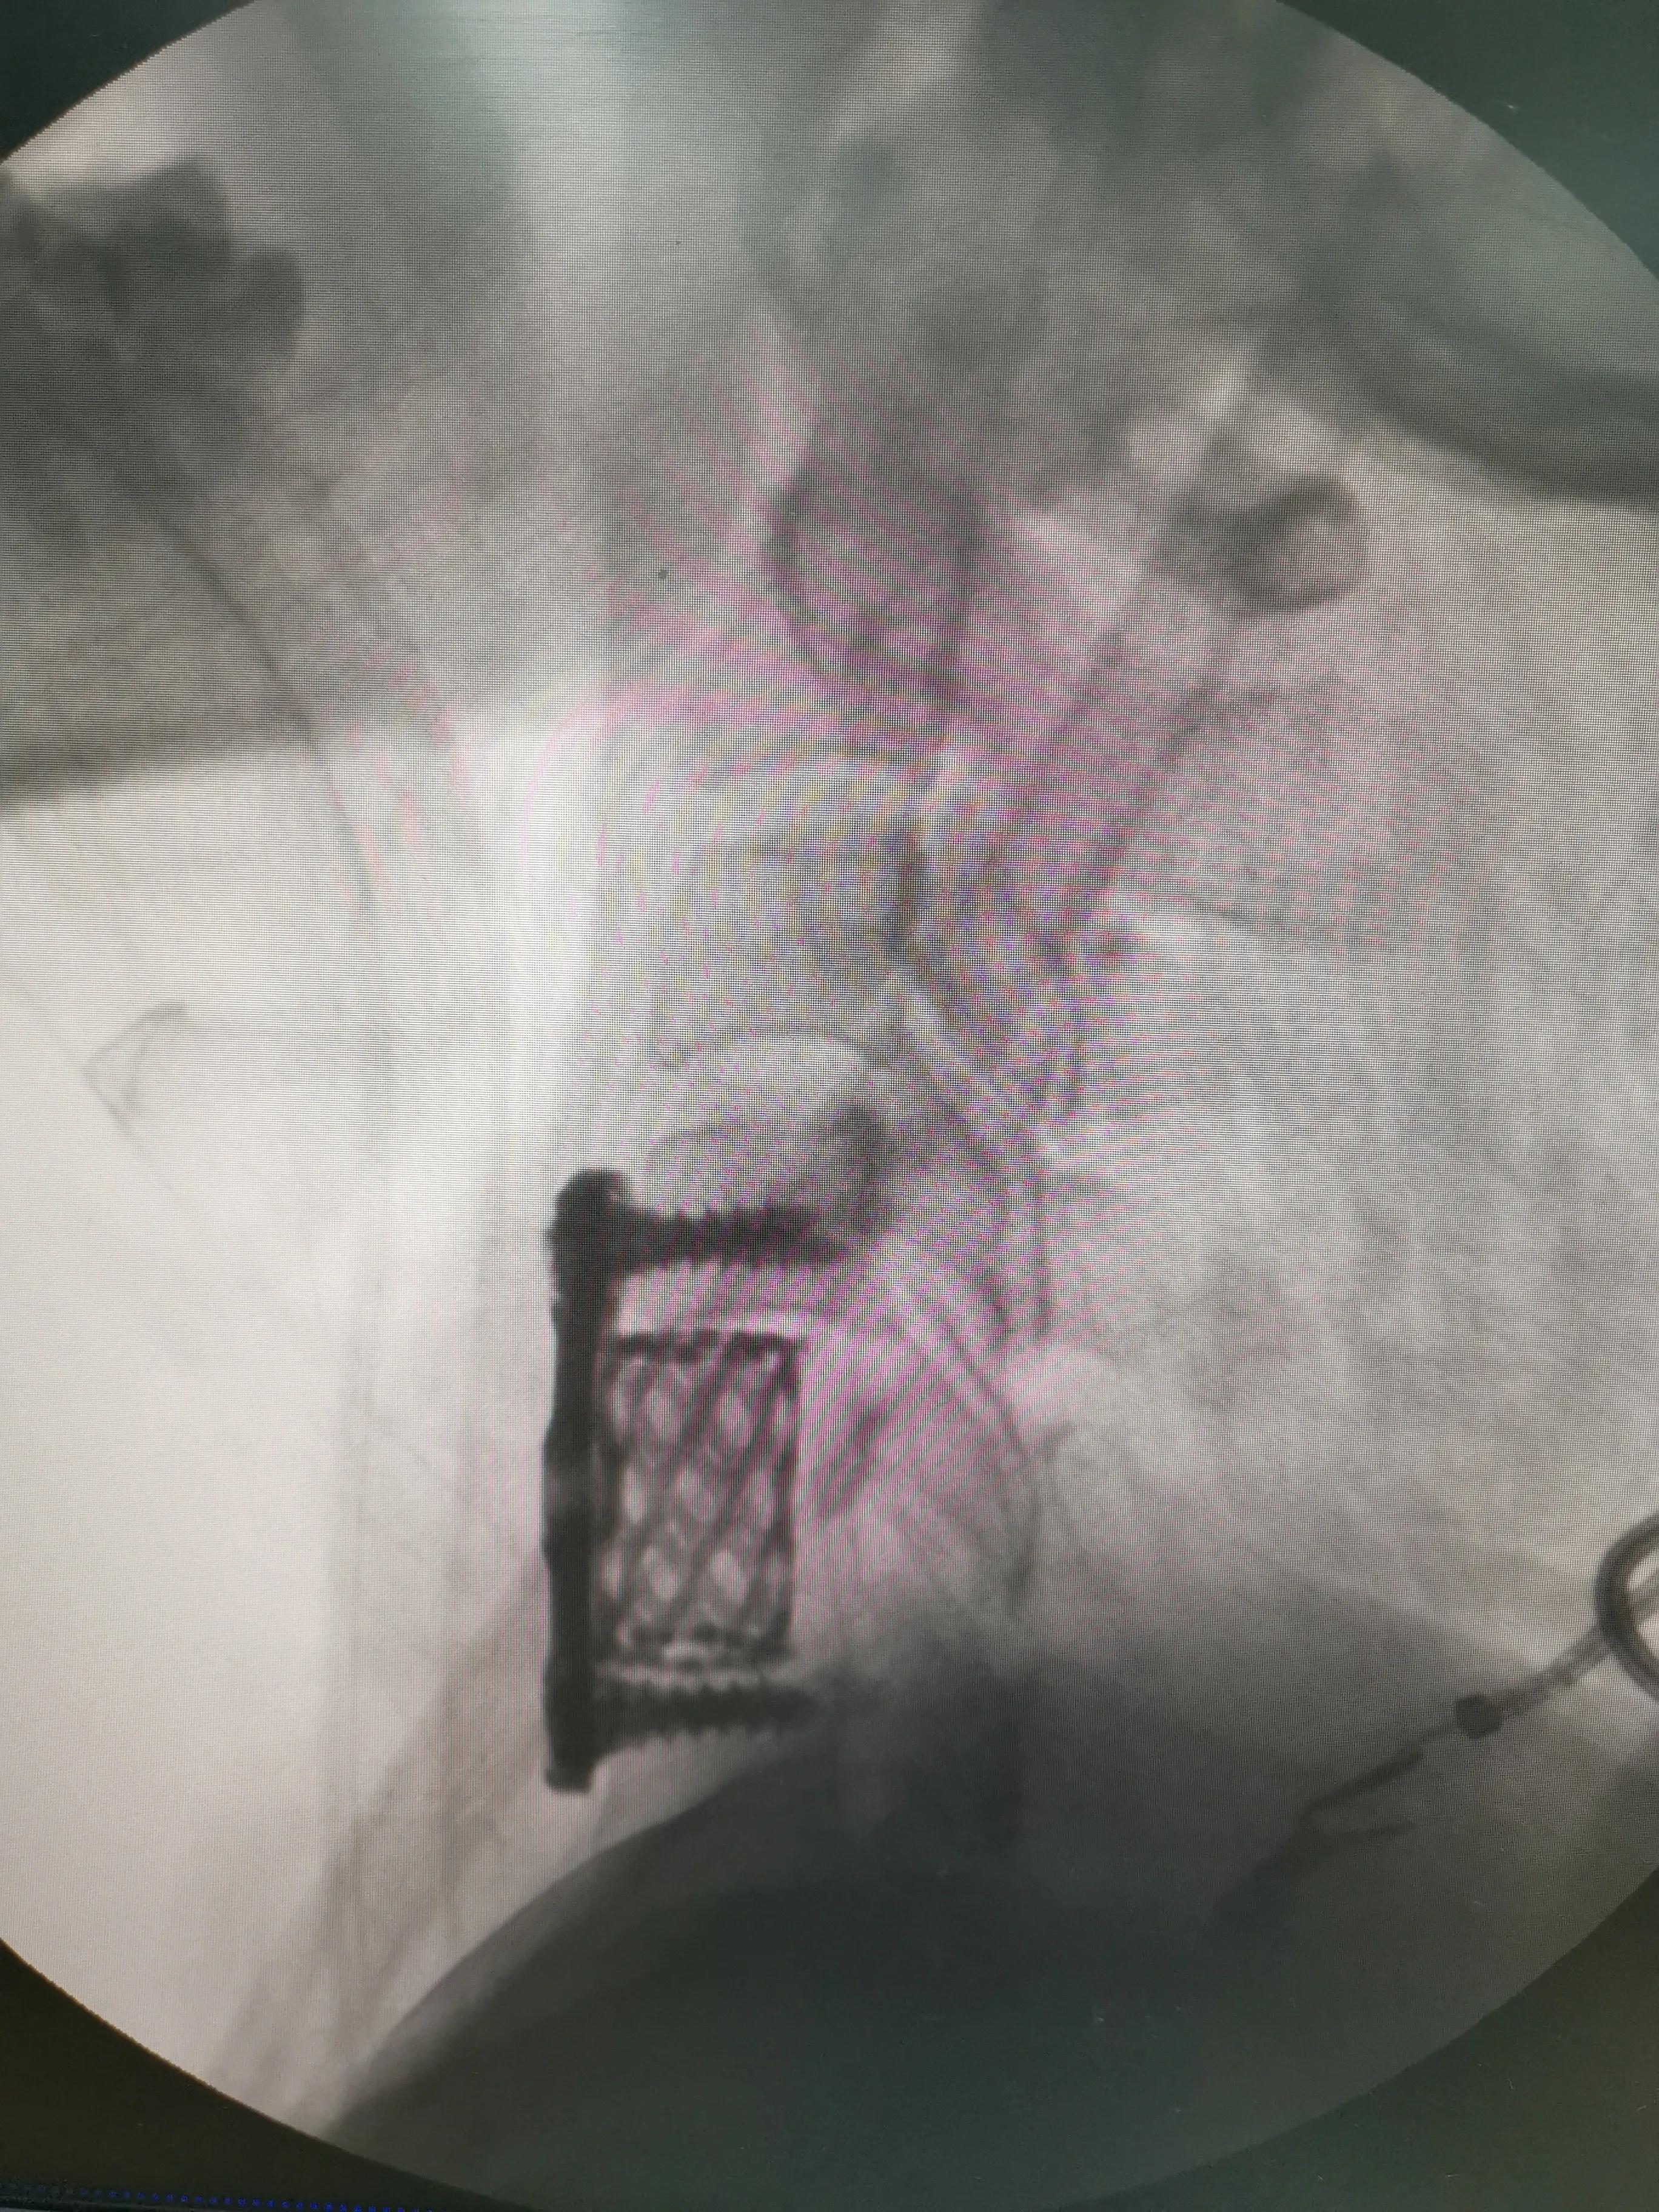

43岁女性,颈肩部疼痛严重伴左侧上肢放射痛无力,mri提示C4/5,C5/6椎间盘突出,CT提示钙化。予前路C5椎体次全切除,椎间盘摘除,椎间钛笼植骨融合钢板内固定,术后疼痛基本消失,肌力逐渐恢复,麻木缓解。

对这类椎间盘突出钙化的患者如果疼痛严重或伴肌力下降或行走不稳,提示压迫神经或脊髓,不宜推拿,可手术减压,效果显著。